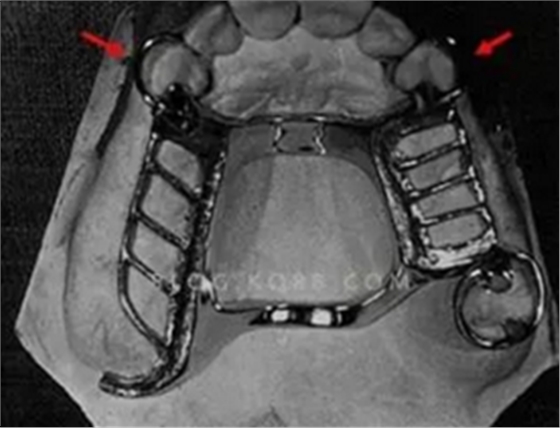

(圖1,引自劉亮大夫,非常經(jīng)典的Kennedy2類力學(xué)設(shè)計方案)

(圖2,4頰側(cè)的固位臂純粹是多余)

在所有游離端基牙的卡環(huán)設(shè)計中,RPI無疑是最被推崇的。RPI的靈魂就是讓游離端鞍基能“無障礙”的下沉,即鞍基受力時僅有合支托受力,其他附件均處于“脫崗”狀態(tài)。若做不到這一點,其他都是狗屁。但RPI制作要求是非常苛刻的,若應(yīng)用不當(dāng)、制作不合理它與傳統(tǒng)三臂卡一樣亦有拔牙作用。①P:盡管鄰面板有三種推薦方案,但鄰面板的齦方與基牙接觸部分在試支架時必須進(jìn)行緩沖,使鄰面板的齦方部分與基牙導(dǎo)平面脫離接觸。因為,負(fù)荷時,鄰面板會以近中牙合支托為圓心產(chǎn)生向近中、齦方的旋轉(zhuǎn)下沉(圖3), 如不緩沖,旋轉(zhuǎn)下沉?xí)r鄰面板會受到基牙的抵觸,如此就會以基牙遠(yuǎn)中面齦方某處為支點以近中合支托為受力點形成類似傳統(tǒng)三臂卡的Ⅰ類杠桿作用,久而久之,基 牙遠(yuǎn)中鄰面牙槽骨吸收,牙齒松動、脫落,“慢性拔牙”作用也即產(chǎn)生。本人是這樣做的:用紅色咬合紙囑病人正中、側(cè)方咬合,調(diào)磨,直至無印記。②I: 負(fù)荷時, I桿的運動軌跡也是以近中牙合支托為圓心產(chǎn)生向近中、齦方的旋轉(zhuǎn)下沉。因此,基牙近中要有可供I桿旋轉(zhuǎn)下沉的足夠倒凹空間,而且, I桿的上端應(yīng)距觀測線0.25mm但絕不能越過此線(妨礙下沉)、遠(yuǎn)中緣不能越過頰軸嵴(妨礙向近中旋轉(zhuǎn))(圖4)。③R:合支托的形狀、與基牙關(guān)系教科書都有(但個人只同意新版教材提到的McCracken<90°設(shè)計)。關(guān)鍵是連接近中合支托的小連接體,與鄰牙應(yīng)有一定的可供“搖擺”空間。否則負(fù)荷運動時與鄰牙接觸的小連接體會對鄰牙施加推力導(dǎo)致其移位。